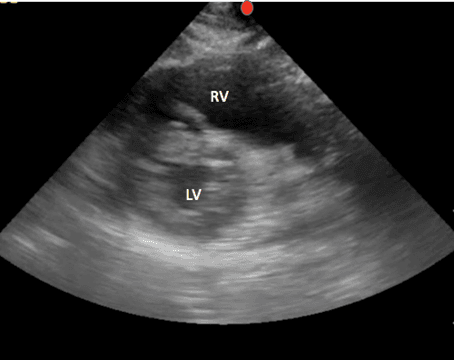

Ausgehend von der Positionierung der parasternalen Langzeitansicht, wobei Ihre Hand an der Brustwand des Patienten verankert ist, drehen Sie die Sonde um 90 Grad, wobei der Indikator nun auf die linke Schulter des Patienten zeigt (Bild 6).

Diese Ansicht ermöglicht die Beurteilung der Funktion des linken Ventrikels, der Symmetrie von Squeeze und der Septumbogenbildung. Der linke Ventrikel ist in dieser Ansicht zu erkennen und erscheint als Kreis unten rechts auf dem Bildschirm. Der rechte Ventrikel erscheint halbmondförmig und befindet sich im oberen rechten Teil des Bildschirms (Bild 7).

PSS-gekennzeichnete Strukturen

Wie beim parasternalen Long kann die parasternale Kurzansicht verwendet werden, um die globale systolische Funktion zu bewerten und Perikardergüsse zu beurteilen. Diese Ansicht ist besonders nützlich, um erhöhte Rechtsventrikeldrücke zu identifizieren, die sich als interventrikuläre Septumabflachung oder Septumbogen manifestieren (Bild 9).